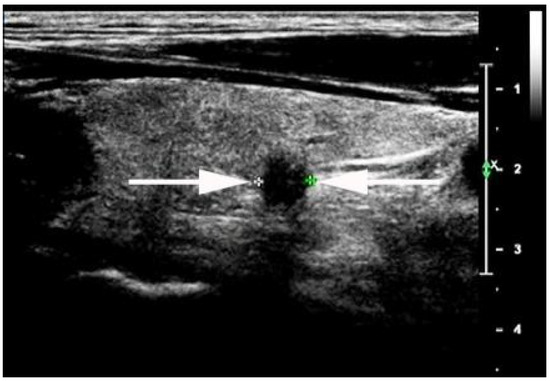

- Chen, S.-P.; Hu, Y.-P.; Chen, B. Taller-Than-Wide Sign for Predicting Thyroid Microcarcinoma: Comparison and Combination of Two Ultrasonographic Planes. Ultrasound Med. Biol. 2014, 40, 2004–2011. [Google Scholar] [CrossRef]

- Kwak, J.Y.; Kim, E.-K.; Youk, J.H.; Kim, M.J.; Son, E.J.; Choi, S.H.; Oh, K.K. Extrathyroid Extension of Well-Differentiated Papillary Thyroid Microcarcinoma on US. Thyroid 2008, 18, 609–614. [Google Scholar] [CrossRef]

- Moon, S.J.; Kim, D.W.; Kim, S.J.; Ha, T.K.; Park, H.K.; Jung, S.J. Ultrasound assessment of degrees of extrathyroidal extension in papillary thyroid microcarcinoma. Endocr Pract. 2014, 20, 1037–1043. [Google Scholar] [CrossRef]

- Chung, S.R.; Baek, J.H.; Choi, Y.J.; Sung, T.Y.; Song, D.E.; Kim, T.Y.; Lee, J.H. Sonographic Assessment of the Extent of Extrathyroidal Extension in Thyroid Cancer. Korean J. Radiol. 2020, 21, 1187–1195. [Google Scholar] [CrossRef]

- Ramundo, V.; Di Gioia, C.R.T.; Falcone, R.; Lamartina, L.; Biffoni, M.; Giacomelli, L.; Filetti, S.; Durante, C.; Grani, G. Diagnostic Performance of Neck Ultrasonography in the Preoperative Evaluation for Extrathyroidal Extension of Suspicious Thyroid Nodules. World J. Surg. 2020, 44, 2669–2674. [Google Scholar] [CrossRef] [PubMed]

- Jeong, S.Y.; Chung, S.R.; Baek, J.H.; Choi, Y.J.; Sung, T.-Y.; Song, D.E.; Kim, T.Y. Sonographic assessment of minor extrathyroidal extension of papillary thyroid micro-carcinoma involving the posterior thyroid capsule. Eur. Radiol. 2022, 32, 6090–6096. [Google Scholar] [CrossRef] [PubMed]